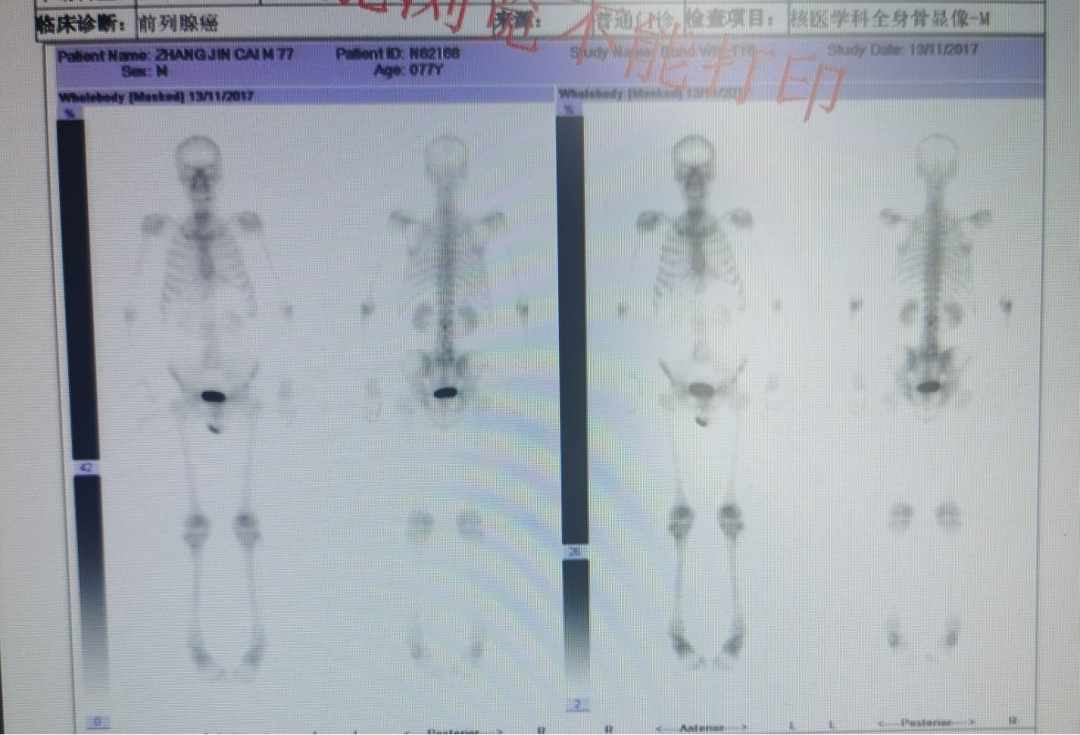

前列腺癌是典型的异质性肿瘤,由于发病隐匿,加之临床筛查工作尚未普及,所以高危进展性前列腺癌及转移性前列腺癌患者所占比例较高。其中,转移性激素敏感性前列腺癌(mHSPC)是转移性前列腺癌中预后较好的类型,但这一阶段的患者进展后将转变为转移性去势抵抗性前列腺癌(mCRPC),患者预后较差。目前,国内外多个权威指南均推荐泽珂®(醋酸阿比特龙片)用于mHSPC及mCRPC的一线治疗。本次为大家带来2例来自真实世界的病例分享,供读者交流和探讨。 病例一 病史 患者男性,78岁,主诉:前列腺特异性抗原(PSA)升高3年余。 现病史:患者3年余前体检发现PSA升高,约4.7ng/ml,后缓慢增高,未重视。2017年6月再次体检提示PSA 28.6ng/ml,外院行前列腺穿刺12针显示为前列腺腺泡腺癌,Gleason score 4+4。SPECT/CT提示全身骨转移(腰2,腰5可疑)。患者长期排尿不畅,夜尿增多(2-3次)。 直肠指诊:前列腺增大,双叶表面触及多处隆起结节质地硬,与直肠关系密切。 辅助检查 血常规:血红蛋白(Hb)126g/L,白细胞计数(WBC)4.7 x 10^9/L,血小板计数(PLT)132x10^9/L。 CT:髂血管旁淋巴结改变。 骨扫描:腰2转移腰5可疑。 图 髂血管旁淋巴结改变 图 全身骨显像 诊断结果 高危mHSPC(T3N1M1b,Gleason评分4+4=8分)。 治疗经过 2017年5月患者于外院应用5月内分泌治疗后,就诊于我院。 2017年11月患者内分泌治疗6月PSA下降至5.7ng/ml,加用原研阿比特龙1000mg联合泼尼松5mg Qd,PSA改善明显,至2020年4月,PSA下降至1.714ng/ml。 2020年7月PSA升至2.765ng/ml,遂将泼尼松换为地塞米松。 2021年4月,PSA为1.667ng/ml,月底更换国产阿比特龙。 2021年7月,PSA升至2.65ng/ml。 2021年8月,PSA为2.635ng/ml,换回原研阿比特龙。 病例分析: 本例患者为高危mHSPC患者,经内分泌治疗后,加用原研阿比特龙,PSA改善明显。国内外权威指南均推荐:醋酸阿比特龙是mHSPC患者的一线治疗方案2-4。LATITUDE研究对比了原研阿比特龙联合泼尼松(AAP)+雄激素剥夺疗法(ADT) vs 单用ADT治疗高危mHSPC患者的结果,数据显示,ADT+AAP显著延长高危mHSPC患者中位rPFS至33个月,对不同亚组的分析显示,ADT+AAP对于不同亚组高危mHSPC患者,均有一致的无进展生存期(PFS)获益,亚洲患者肿瘤转移进展风险降低近七成。原研阿比特龙组至PSA进展时间为33.2个月,对照组7.4个月,降低PSA进展风险70%。总生存期(OS)数据显示,安慰剂组中位OS为36.5个月。原研阿比特龙组为53.3个月,P值具有显著的统计学差异5。 图 LATITUDE研究结果 该患者使用原研阿比特龙32个月后,PSA显著改善,换用国产阿比特龙,PSA水平升高,这提示我们仿制药和原研药之间存在差异。原研阿比特龙是国际国内指南一线推荐治疗晚期前列腺癌的新型内分泌药物,相比仿制品,具有卓越的疗效及安全性证据。真实世界中,相比原研阿比特龙,仿制阿比特龙发生更多严重不良事件6-7。 病例提供者:马宏 教授 马宏 教授 北京医院泌尿外科 副主任医师 北京肿瘤防治研究会泌尿肿瘤委员会 副主委 北京抗癌协会泌尿肿瘤青年委员 北京中西医结合男科分会青年委员 中国研究型医院学会泌尿及男科冲击波学组委员 《中国性杂志》编委 北京大学医学部优秀教师 台大医院,柏林夏洛蒂医院访问学者 点评(万奔教授) 国产仿制药对于临床医生,多了可供选择的空间;对于患者,降低了部分支付压力。通常,仿制药的生物利用度在原研药生物利用度的80%~125%之内都认为两者具有生物等效性,但生物等效性在判定原则上会导致仿制药与原研药的生物利用度存在差异,而且会导致仿制药之间的生物利用度差异更大。在该病例中,患者换用国产阿比特龙后,PSA水平升高,提示生物等效性≠临床等效性8。对于部分高龄前列腺癌患者,基础合并疾病较多,生活质量普遍较差,如果非医疗原因换药,导致疾病波动及发生并发症的风险显著提高。因此,临床上应重点关注以上类型患者,谨慎权衡仿制药或原研药的选择9-12。期待未来中国制药产业技术的不断革新,国产仿制药品从品种到品质可以比肩原研药,保障更多患者获益。另外,此病例提示,阿比特龙联合治疗时,糖皮质激素的替换可带来患者的持续PSA减低。 点评专家:万奔 教授 万奔 教授 北京医院泌尿外科 主任医师 中国医师协会泌尿外科医师分会肿瘤专业委员会 委员 中国研究型医院学会泌尿外科学专业委员会 委员 北京抗癌协会泌尿男生殖系肿瘤专业委员会 副主任委员 北京医师协会泌尿外科专家委员会 委员 海峡两岸医药卫生交流协会泌尿外科学专业委员会 委员 中日医学科技交流协会 理事 病例二 病史 患者男性,69岁。主诉:体检发现PSA升高1周。 既往史:冠心病8年,3年前于外院行心脏冠脉支架置入术,长期口服阿司匹林和波利维抗血小板治疗。 辅助检查 实验室检查:总前列腺特异性抗原(T-PSA)149.5ng/ml。 骨扫描:右侧第3-5前肋、左侧第3/6前肋、第7后肋、第9后肋近肋椎关节处、第10胸椎、第2/5腰椎放射性摄取增高影(10处)。 前列腺MR增强:前列腺癌可能大,肿瘤突破包膜,累及精囊腺。双侧髂血管旁多发肿大淋巴结,转移可能。腰2、5椎体骨质破坏,转移可能大。 图 全身骨显像 穿刺病理:前列腺癌,12/13(+),Gleason 评分 4+5=9分,部分可见肿瘤浸润神经。 诊断结果 第一次诊断(2014年6月):高危mHSPC(T3bN1M1)。 第二次诊断(2015年2月):mCRPC。 治疗经过 2014年6月接受比卡鲁胺50mg Qd x 2w+戈舍瑞林10.8mg治疗。 2014年7月入组LATITUDE研究,PSA最低降至4.02 ng/ml。 2015年2月复查PSA升高至14.73 ng/ml,试验出组,揭盲,证实为安慰剂组;随后患者接受戈舍瑞林10.8mg+比卡鲁胺50mgQd,6个月后,PSA最低达到4.21 ng/ml。 2015年12月PSA升至9.12 ng/ml,停用比卡鲁胺,PSA水平于2016年2月回落至6.5ng/ml,8周后PSA再度上升至11.97ng/ml。 2016年6月患者接受阿比特龙1000mg Qd+泼尼松5mg Bid,PSA逐渐降低,最低至0.75ng/ml。 2017年11月将泼尼松5mg Bid换为地塞米松0.75mg Qd,PSA为2.36ng/ml。 2019年12月PSA水平缓慢上升到18.49 ng/ml,开始多西他赛+地塞米松方案化疗患者完成DP方案9周期化疗,PSA降至1.72ng/ml。 2020年7月患者因下腹隐痛行盆腔磁共振及PSMA-PET/CT检查示新发精囊转移灶,行放疗后,发现精囊癌灶变小,盆腔疼痛症状消失。 2020年11月PSA升高至3.4ng/ml,伴随新发后肋部疼痛,需口服镇痛药物缓解。复查PSMA和SSTR-PET/CT发现新发后肋部转移灶及多发肝脏病灶 ;行CT引导下肝脏病灶穿刺活检;病理:肝组织内见癌细胞浸润。 2020年11月23日多西他赛120mg+卡铂450mg化疗,化疗1周后出现中性粒细胞减低、血小板减低 CTCAE IV级,对症支持治疗1月后好转。 2021年1月开始应用恩杂卢胺治疗。 …… 图 前列腺癌患者不同治疗方案期间血清PSA水平变化情况 病例分析: 本例患者就诊时即发现全身多发骨转移,且Gleason评分4+5=9分,符合高危及高肿瘤负荷mHSPC诊断,2014年7月患者入组LATITUDE研究。LATITUDE研究为一项在新确诊为高危转移性未经激素治疗的前列腺癌患者中进行的多中心、3期、随机、双盲、安慰剂对照试验。最终分析显示,一线接受ADT+AAP的患者中位OS达4.5年,比一线接受ADT的患者延长16.8个月。因此,该患者无论接受单纯ADT,还是联合雄激素阻断治疗(CAB)都是不足够的,应首选推荐ADT联合阿比特龙的治疗方案。 图 LATITUDE研究结果 患者在mCRPC阶段应用阿比特龙联合泼尼松,经过数年的治疗,PSA控制良好,中间泼尼松换用地塞米松,继续维持阿比特龙使用,直至出现症状及影像进展。患者历经新型内分泌治疗等多种疗法,实现了长达7年的长期生存1。 病例提供者:米悦 教授 米悦 教授 北京大学第一医院 泌尿外科 主治医师 博士 北京大学泌尿外科研究所 擅长泌尿系肿瘤的微创治疗,前列腺增生、泌尿系结石的腔内治疗及晚期肿瘤的综合治疗。一直从事泌尿外科临床医疗、教学和科研工作。 2018年参加第32届“中国泌尿外科将才工程培训班”赴美国USC访问交流。累计发表国内核心期刊论文及SCI 论文6篇,参与撰写泌尿外科专著3部,翻译4部泌尿外科专著。 点评(张骞教授) 本例患者第一次被确诊为mHSPC,ADT治疗7个月后疾病快速进展为mCRPC。大部分高危/高瘤负荷的mHSPC患者在治疗初期ADT产生应答,但在ADT治疗9~15个月后发展为mCRPC。因此,对于高危mHSPC患者,临床应更早使用新型内分泌治疗。无论以PSA下降超过30%或50%作为界值,达到早期PSA应答(EPR)的患者预后均显著优于未达到EPR的患者。当患者进入mCRPC阶段后,应用ADT+AAP方案治疗1个月,患者PSA水平下降幅度达到73.4%,实现了EPR并且PSA较基线下降>50%。此后该方案在近3年内持续保持肿瘤相对控制和疾病稳定状态。该患者历经新型内分泌治疗、化疗、放疗、联合化疗和新型内分泌序贯治疗,取得了较好治疗效果,实现了长期生存。 点评专家:张骞 教授 张骞 教授 北京大学泌尿外科研究所 副所长 北京大学第一医院泌尿外科 副主任 北京大学滨海医院 院长 北京大学医学部医院管理处 处长 郭应禄泌尿外科发展基金会 副理事长 中国医师协会泌尿外科分会青年委员会 副主任委员 中华医学会泌尿外科学分会微创学组 委员 国家卫计委泌尿外科内镜诊疗技术专家组 委员 中国医促会腔镜内镜分会 常委 编者手札 在转移性前列腺癌患者的治疗过程中,通过监测PSA水平和影像学检查变化,能够及时了解患者对雄激素的敏感程度和疾病的进展情况,为治疗方案的调整和预后判断提供依据。原研阿比特龙是国际国内指南一线推荐治疗晚期前列腺癌的新型内分泌药物,首选原研阿比特龙能够为患者带来明显的PSA下降和持续的疾病控制。 备注:文中醋酸阿比特龙片简称阿比特龙 参考文献: 1.米悦,等.中华泌尿外科杂志.2021;42:19-23. 2.Advanced Prostate Cancer: AUA/ASTRO/SUO Guideline.2020. 3.European Association of Urology. Guidelines on Prostate Cancer. 2021. 4.NCCN Clinical Practice Guidelines in Oncology(NCCN Guidelines®) .2021.v2.. 5.CSCO,2021 前列腺癌诊疗指南 6.https://www.fda.gov/drugs/surveillance/fda-adverse-event-reporting-system-faers 7.Ryan CJ, et al. Lancet Oncol. 2015; 16(2):152-160. 8.黄浪,等.北方药学.2011;08(8):83-84. 9.resented by Prof. Gao Xin at 2018 CACA GU annual conference, Shanghai, Dec. 8, 2018. 10.马宝杰,等.中华泌尿外科杂志.2014;000(007):554-556. 11.Cheng Y, et al. Pharmacoepidemiol Drug Saf. 2019;28(11):1501–1509. 12.Holm M, et al. BMC Palliat Care. 2018 Dec 3;17(1):126.